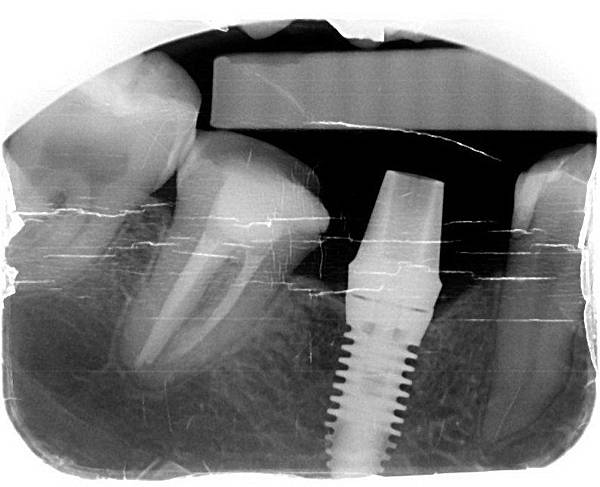

X光片系列

X光片系列

完成圖 X光片系列

X光片系列